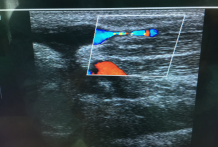

附图

(一) 暨南大学第一附属医院胡波博士指导超声引导下球囊扩张术

(三) 手术前后血管对比示意图